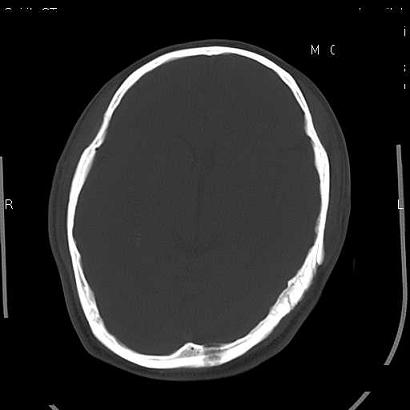

男,39岁,外伤来诊,老师们看看枕骨是什么病

枕内隆突左缘板障区示不规则囊状透亮区,颅骨内外板规整,无膨胀及缺损,周围无软组织肿块,考虑板障血管性病变,1.板障静脉湖,2.枕骨血管瘤(局部无膨胀性改变,无硬化环及钙斑影,故不太支持)。

蛛网膜颗粒压迹不会象这样有清晰的内板显示的!压迹压迹肯定是把内板压到板障里撒!各位老师同意不?